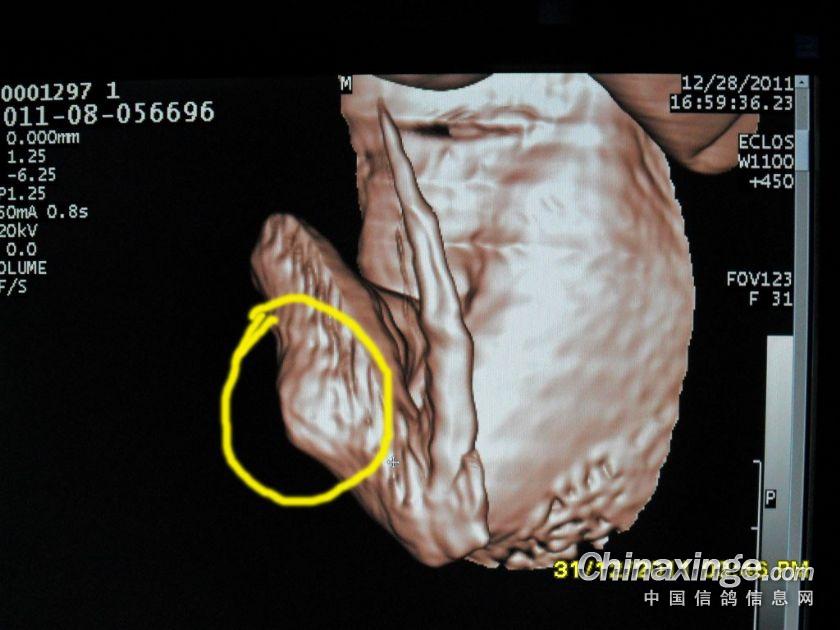

作品说明: 2011年秦皇岛BOB公棚四关宾利汽车大奖赛 2011-08-056696 雨点 雌 第一关 08-056696 116名 第二关 08-056696 59名 双关综合冠军 第三关 08-056696 37名 三关综合冠军(领先亚军332名,3天共归巢292羽) 第四关 08-056696 未归?开笼后只飞行了几公里被迫落下!被人拾到后发现“没有盖暗记的翅膀”内侧已经肿胀并且有一个疙瘩!!!

左侧肿胀的翅膀

钢针插在翅膀内,翅膀肿胀,开笼后被迫落下!!!

肿胀翅膀的外表

肿胀翅膀内侧的包